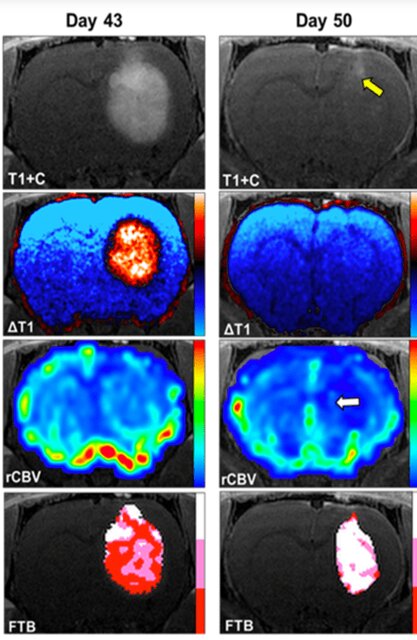

این گروه پژوهشی به سرپرستی "کریستوفر چیتامبار"(Christopher Chitambar)، پژوهشگر کالج پزشکی ویسکانسین، فرآیندهای مبتنی بر آهن را در زیستشناسی سرطان و مکانیسمهایی که ترکیبات "گالیوم"(Gallium) را هدف قرار میدهند و رشد بدخیم سلول را متوقف میکنند، مورد بررسی قرار دادند. چیتامبار و "کاتلین اشمایندا"(Kathleen Schmainda) دریافتند که ترکیب موسوم به "مالتوات گالیم"(Gallium maltolate)، پیشروی و کاهش گلیوبلاستوما را به طور قابل توجهی کند میکند.

چیتامبار گفت: کشف این موضوع که مالتوات گالیم دارای فعالیت ضد سرطانی در برابر گلیوبلاستوما است، موضوع بسیار هیجانانگیزی به شمار میرود و راه را برای توسعه آن به عنوان دارویی برای درمان گلیوبلاستوما در بیماران هموار میکند. مکانیسم ضد سرطانی مالتوات گالیم، برای سایر تومورهای جامد نیز کاربرد دارد.